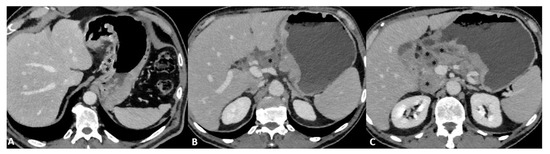

Figure 2.

T3 gastric cancer in a 72-year-old male patient. (A) Axial 2D image in the portal venous phase and (B) Coronal 2D reconstruction showing wall thickening (white arrow) in the lesser curvature of the low body of the stomach and inhomogeneous enhancement. The tumor invades the subserosa layer without invasion of the serosa and adjacent structures.

Figure 3.

T3 gastric cancer in a 74-year-old female patient. (A) Coronal 2D reconstruction in the portal venous phase and (B) Axial 2D image showing (thick arrows) enhanced wall thickening in the lesser curvature side of the high body of the stomach. (B) also shows a cluster of pathologic round lymph nodes adjacent to the gastric cancer (thin arrows). The tumor invades the subserosa layer without invasion of the serosa and adjacent structures.